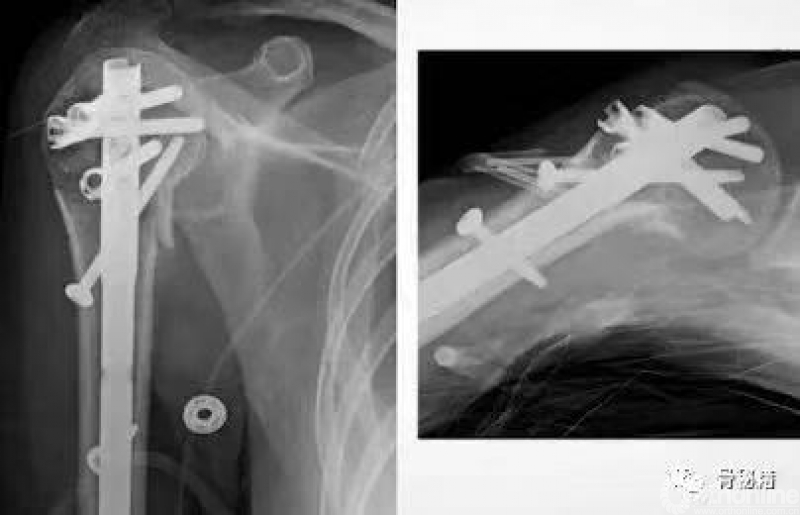

再说说设计方面

在螺钉的固定方面,Multilock的多平面螺钉与philos的固定已经基本接近了

multilock的螺钉前方是顿头的,不会穿破关节

其后方也有缝线孔,可以结合缝线用来固定肩袖、大结节等组织